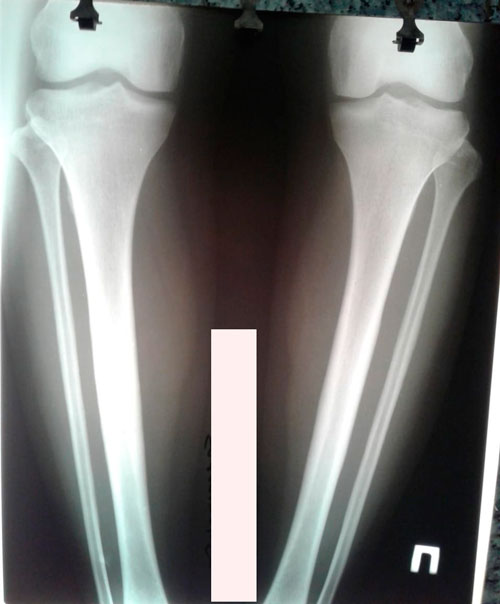

Исходник-28 лет.Павлодар.

Дата операции - 08.10.2018г.

Дата снятия аппаратов - 07.01.2019г.

Срок сращения - 90 дней.